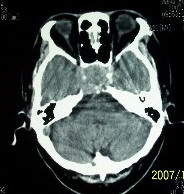

f    29岁   头闷  头晕1月余

肿瘤累及颅底前颅窝,部分层面见散在钙化,中心坏死。支持:脑膜瘤!

右额叶底部巨大等低混杂密度肿块,边界清楚,周围水肿轻度,明显占位效应。蝶鞍扩大,部分骨质破坏。

考虑脑膜瘤,建议增强扫描进一步检查。

蝶鞍受压吸收,可以排除室管膜瘤。肿瘤最大层面不在蝶鞍可以排除垂体瘤。支持脑膜瘤